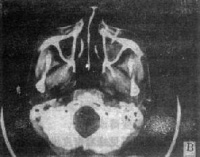

4.X线摄片示上颌窦腔密度增高、软组织肿块影及窦壁骨质破坏

详细检查前后鼻腔,大多数病例有鼻腔异常,鼻腔外侧壁内移致鼻总道狭窄。当瘤侵入鼻腔时可通过前鼻孔或后鼻腔检查直接窥见。瘤体位于鼻腔侧壁或顶壁,呈灰红色,表面粗糙;或呈烂肉状,触之易出血;有时表面覆有污秽灰膜,伴组织坏死。鼻中道或鼻下道可见血性分泌物或血痂,或见鼻息肉样肿块,实为恶性肿瘤。因息肉样变与鼻息肉可与上颌窦肿瘤并存。因此,体格检查往往可早期发现异常表现,若鼻腔检查无特殊,也不能完全除外上颌窦恶性肿瘤,只要有临床症状,则宜作进一步检查。